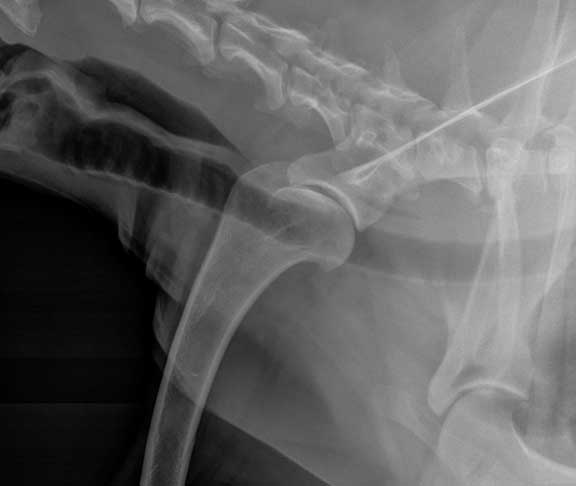

Normal Canine Shoulder